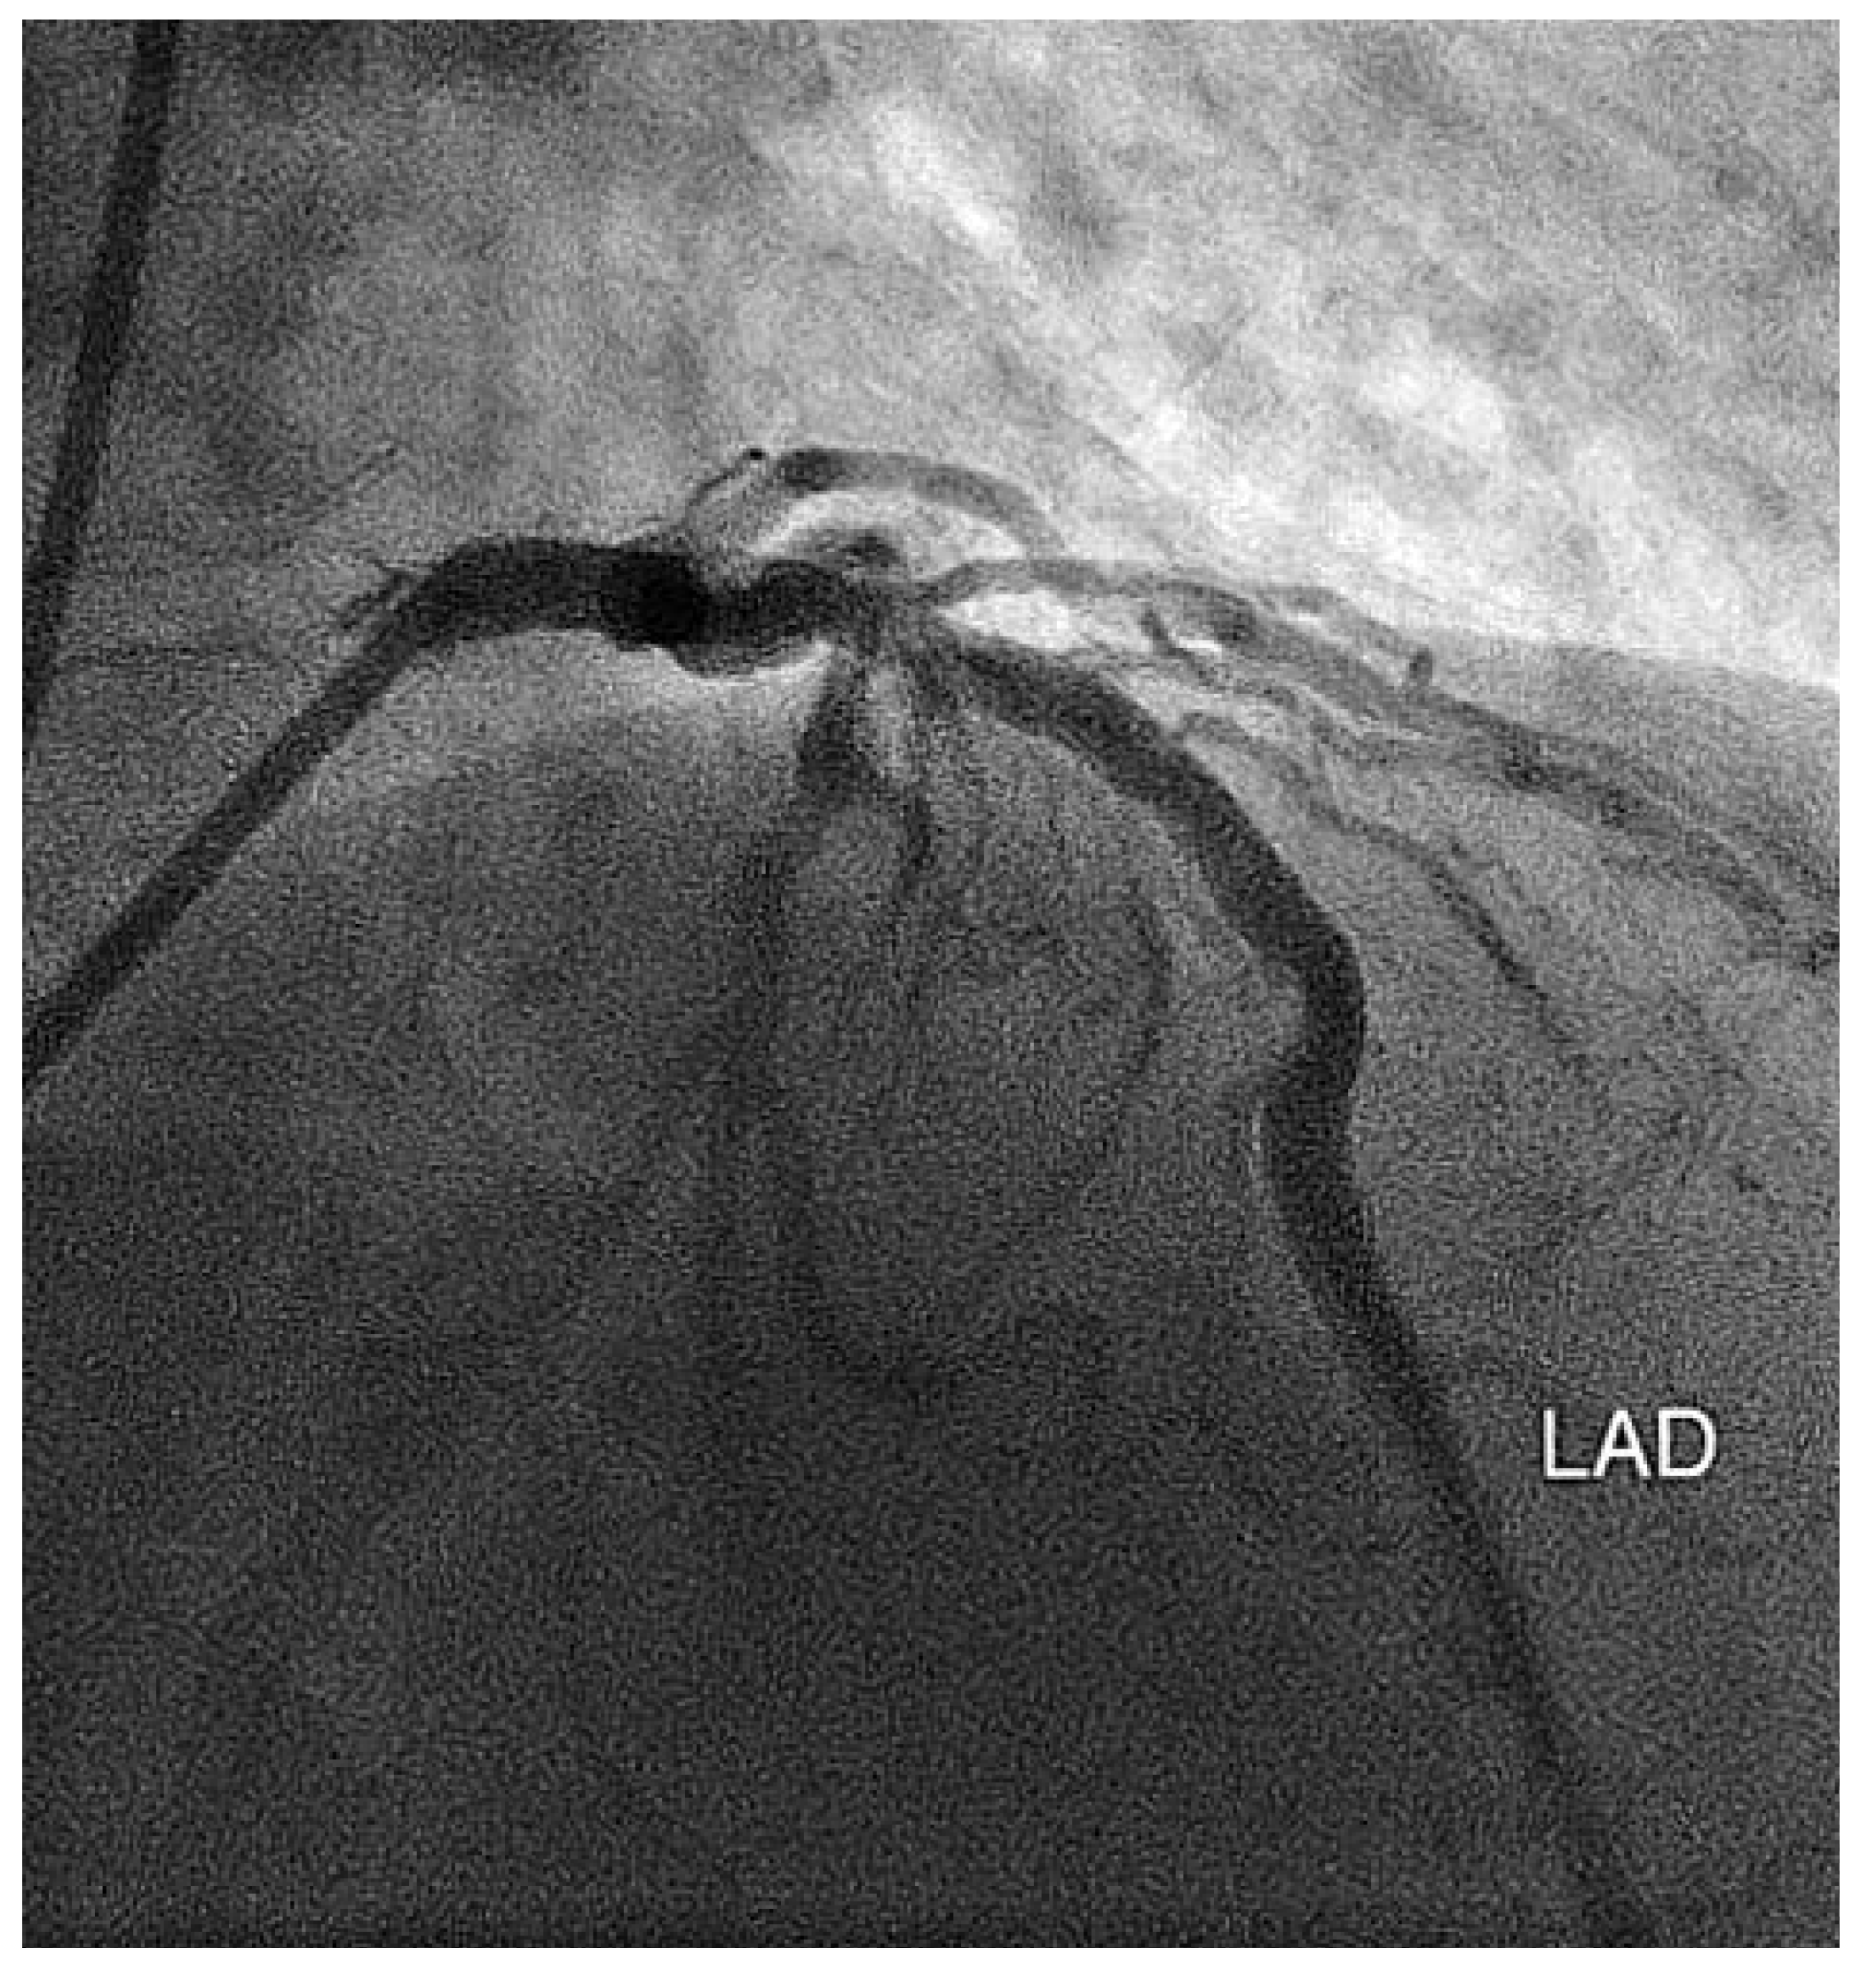

Koronarstenose Und Transthorakale Farbdopplerechokardiographie

Fallbeschreibung